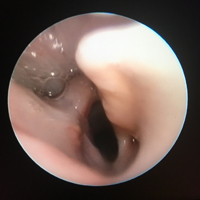

• ENT Surgery; BOAS surgery, stick injuries, salivary mucocoeles, TECA/LBO, rhinoscopy, aural and ocular surgery